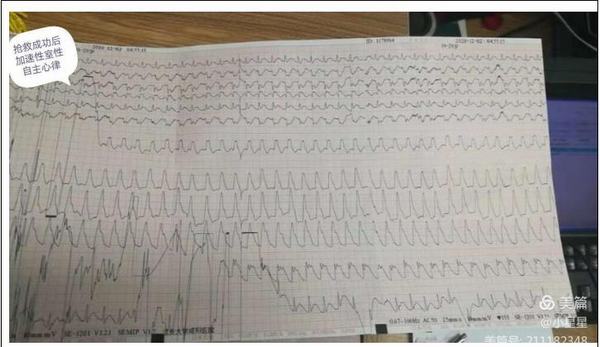

15分鐘后,患者王先生在家屬的陪同下來到了延安大學咸陽醫院心血管病院11樓心六科,在吳醫生問診及查體時患者胸痛再次發作,并于4點20分突然出現四肢抽搐、呼之不應,觸摸頸動脈搏動消失,呼吸呈嘆息樣,立即予以心肺復蘇術,心電監測提示心室停搏,與此同時我科楊登魁責任總醫師、我院心一科王銀濤醫師、心二科代雪茹醫師、心三科王巖醫師、留夜護士陳娜、心七科徐云鵬醫師、留夜護士高謙聞訊趕來,并立即投入緊張的搶救過程中,經予持續胸外按壓、多次電除顫等治療后患者于4點40分意識逐漸恢復,心電監測示加速性室性自主心律,搶救成功,而早己就位的導管室同仁也做好了準備工作,并于6點40分成功開通了患者閉塞血管,術后患者生命體征平穩。